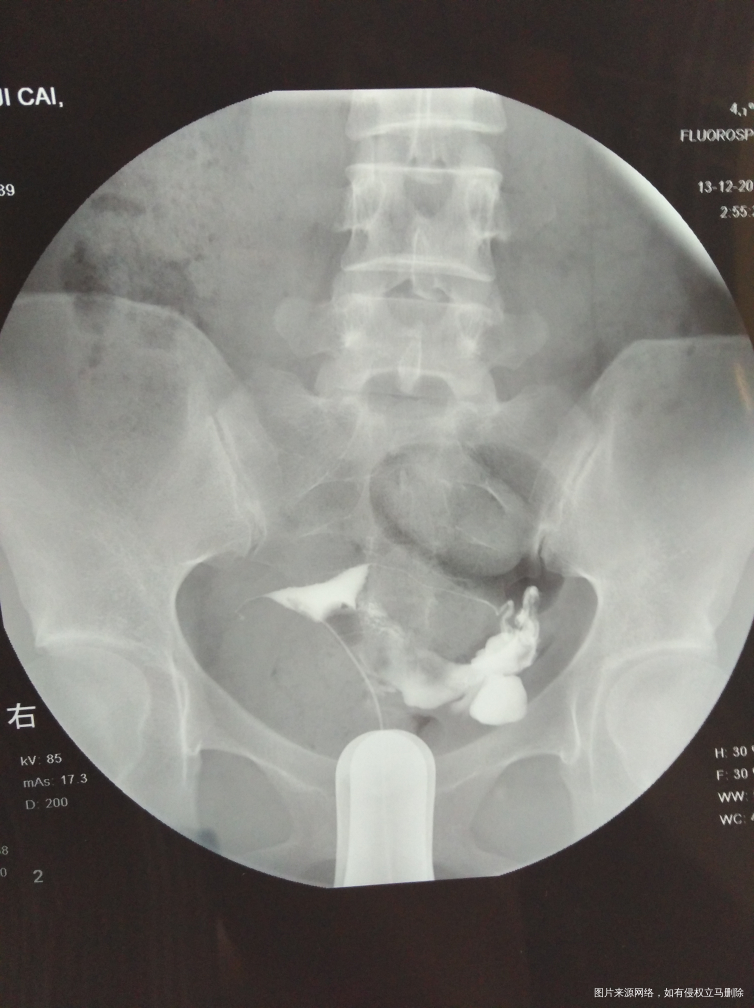

麻烦医生指点,输卵管通而不畅要怎么治疗?我的右侧输卵管部分切除,所有希望都寄托在这跟管上了,我不想试管,想自然怀孕,帮帮忙指点

,谢谢!从哪里看的出通而不畅的,也帮忙指点一下

您好,你这种情况考虑试管婴儿比较合适您,从图上看还有盆腔炎,如果你不想试管坚持自己试可以考虑手术,术后自然妊娠几率低,请慎重考虑

你好,从您的片子看,盆腔弥散局限,所以输卵管通而不畅。可以选择中药治疗。最多半年,如果不怀,可以选择手术或者试管。祝您早日好孕。如果满意我的回复,记得采纳。

你好,从您的片子看,盆腔弥散局限,所以输卵管通而不畅。可以选择中药治疗。最多半年,如果不怀,可以选择手术或者试管。祝您早日好孕。